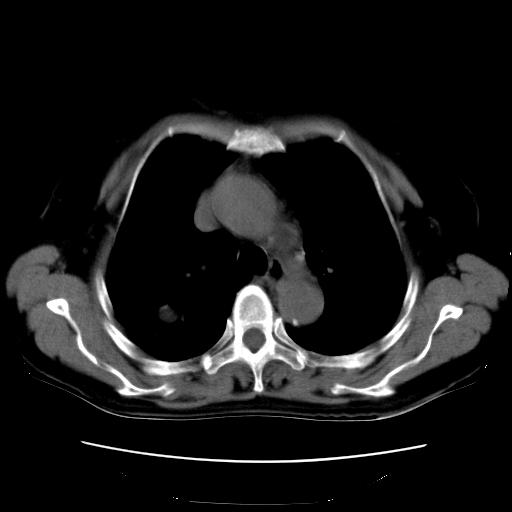

以下是引用卜一在2007-9-18 14:41:00的发言:[br]右肺肿块:毛刺+胸膜凹陷征+供血血管+浅分叶+强化。支持:周围性肺癌 !另:左侧甲状腺腺瘤!

以下是引用夏季在2007-9-18 11:00:00的发言:[br]1。右肺肿块,周围有短毛刺,肺门侧有血管与其相连,胸壁侧有胸膜凹陷征,考虑周围性肺癌 2。左侧甲状腺软组织肿块,内有高密度钙化灶,考虑左侧甲状腺腺瘤。